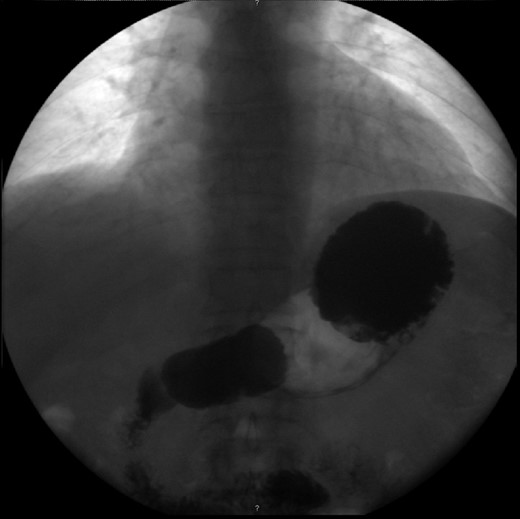

Haematological and biochemical profiling were performed, as well as plain abdominal radiographs (Fig. 4) and abdominal ultrasound, all showing no relevant changes. The upper endoscopy revealed a mild esophagitis. An upper gastrointestinal series was later executed, revealing the presence of an organoaxial volvulus (Fig. 5).

Upper gastrointestinal series, revealing an organoaxial torsion of the stomach.